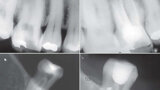

Fig. 11 : Cas clinique Dr Carlos Spironelli.